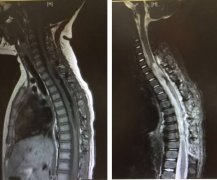

髓内脊髓肿瘤(IMSCTs),如下图所示,是指硬膜内 脊髓肿瘤 的一个亚群,由脊髓内的细胞产生,与相邻结构如神经根或脑膜相对。它们比脑瘤少见得多,据认...

脊髓肿瘤 是在脊髓内或周围发生的非癌性(良性)或癌性(恶性)生长。人们可能会有肌肉无力,失去身体特定部位的感觉,或无法控制肠道和膀胱的功能。磁...